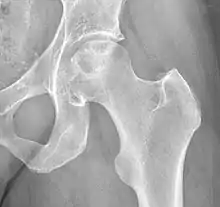

Chandler's disease otherwise known as Idiopathic Avascular osteonecrosis of the femoral head (ANFH or ONFH) is a rare condition in which the bone cells in the head of the femur (FH) die due to lack of blood. This disease is caused when blood flow is reduced to the part of a bone near a joint. It is specifically unique because the femoral head is for some reason the only affected part of the body and rarely travels down to the main part of the femur. In 1948 F.A. Chandler did a multi-case review and first released his interpretations as Coronary Disease of the Hip. Although now we know his term is incorrect and improperly describing the actual disease.[1]

The current etiology or origin of this disease is unknown. Some studies theorized that bone remodeling is maintained in a microenvironment in the FH meaning that there is a greater local component to changes to the femoral head than the normal systemic way that bone remodeling is handled throughout the body. As a whole our body goes through bone remodeling using various hormones and glucocorticoids to balance the uptake and output of bone throughout the entire body. The local portion is considered to be controlled partially by inflammatory cells called cytokines and individual growth factors. The theory is that the local bone remodeling is malfunctioning and overpowering the systemic bone remodeling causing the FH to be highly susceptible to necrosis. Studies have determined that there are risk factors that are more than likely associated with the development of the disease but many of them are very broad and include large groups of people for example alcoholics, diabetics, and many other common core morbidities. Unfortunately, most are classified under idiopathic due to being unable to truly narrow down the origin of why it only happens to the head of the femur. What most clinicians observe is that the head of the femur seems to almost have a system of its own somewhat separate from the rest of the femur. There are many theories as to how the head of the femur dies unlike why it is happening.[3]